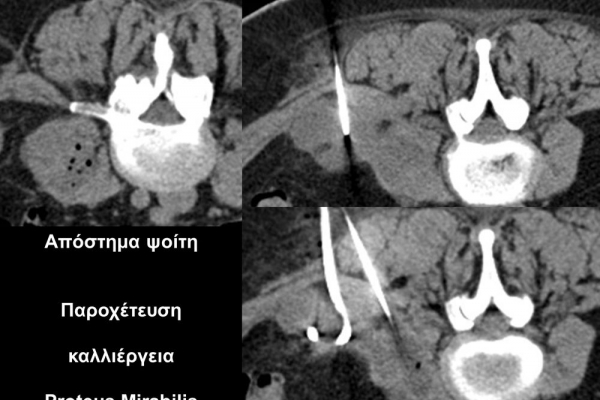

Η οστική βιοψία και η βιοψία όγκων μαλακών μορίων χρησιμοποιείται για την ιστολογική διάγνωση αλλοιώσεων (καλοήθων - κακοήθων / πρωτοπαθών ή μεταστατικών) ή για τη λήψη υλικού προς καλλιέργεια ώστε να αναδειχθεί το μικρόβιο που προκαλεί τη λοίμωξη του μυοσκελετικού συστηματος (πχ σπονδυλοδισκίτιδα). Η βιοψία υπό συνεχή απεικονιστική καθοδήγηση συμβάλλει στην υψηλή ακρίβεια τοποθέτησης της βελόνης εντός της βλάβης με ασφαλή προσπέλαση. Η χρήση σύγχρονων ομοαξονικών συστημάτων βιοψίας (coaxialtechnique) επιτρέπει την λήψη πολλαπλών δειγμάτων με μια μόνο παρακέντηση.